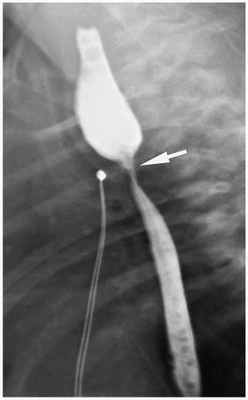

Скопия

Пищевод визуализируют при помощи водорастворимых контрастных веществ (около 0,5 мл), которые немедленно должны быть аспирированы сразу после проведения исследования. После аспирации секрета в проксимальную часть пищевода вводят 1-2 мл воздуха для визуализации расширенного, заполненного воздухом пищевода. Исследование может показать слепое окончание проксимального отдела пищевода и / или может указать на наличие о трахеоэзофагеальной фистулы. Скопия особенно полезна при демонстрации H-типа атрезии.

Также проводится рентген-контрастное исследование. Через зонд в верхний сегмент пищевода вводится не более 1 мл контраста. При наличии верхнего трахеопищеводного свища, кроме пищевода окрашивается ещё и трахеобронхиальное дерево.

Если после начала кормления ребёнка в интубационной трубке появляется смесь, можно заподозрить, что трахеопищеводный свищ образовался снова. О нарушении герметичности анастомоза говорит появление слюны в страховочном дренаже в зоне анастомоза. В таких случаях для дополнительной диагностики проводится рентгенологическое исследование с использованием водорастворимых контрастных веществ. При обнаружении «утечки» проводится повторное оперативное вмешательство с целью устранения несостоятельности швов на пищеводе или трахее.

После операции продолжалась интенсивная терапия. При благоприятном течении послеоперационного периода кормление через зонд начиналось через 3–5 суток после операции. На 8–9 сутки проводилась эзофагография с целью определения состоятельности анастомоза. Для этого под контролем рентгеновского экрана через рот ребенку вводилось 1–2 мл водорастворимого контрастного вещества. Оценивалась проходимость анастомоза пищевода, исключались затеки контрастного вещества в средостение. При отсутствии осложнений ребенок начинал кормиться через рот.